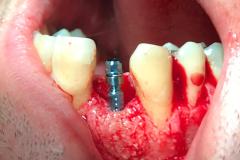

Immediate implant placement with simultaneous bone augmentation and connective tissue grafting. The case will be completed with crown lengthening, veneer replacement, and soft tissue optimisation to achieve ideal emergence profiles.